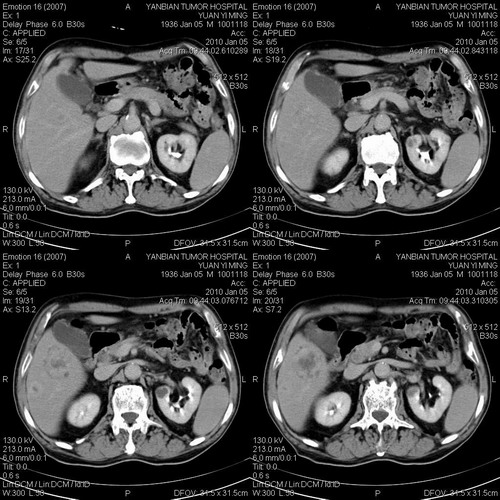

标题: CT24024:男,74岁。体检超声发现肝内多发占位性病变四天。 [打印本页]

标题: CT24024:男,74岁。体检超声发现肝内多发占位性病变四天。

考虑肝多发血瘤可能,未除转移瘤。

并肝肾囊肿。

1)考虑肝脏恶性肿瘤(转移瘤?)。2)肝外胆管轻度扩张。3)左肾小囊肿。

考虑肝脏恶性肿瘤(转移瘤?)。2)肝外胆管轻度扩张。3)左肾小囊肿。